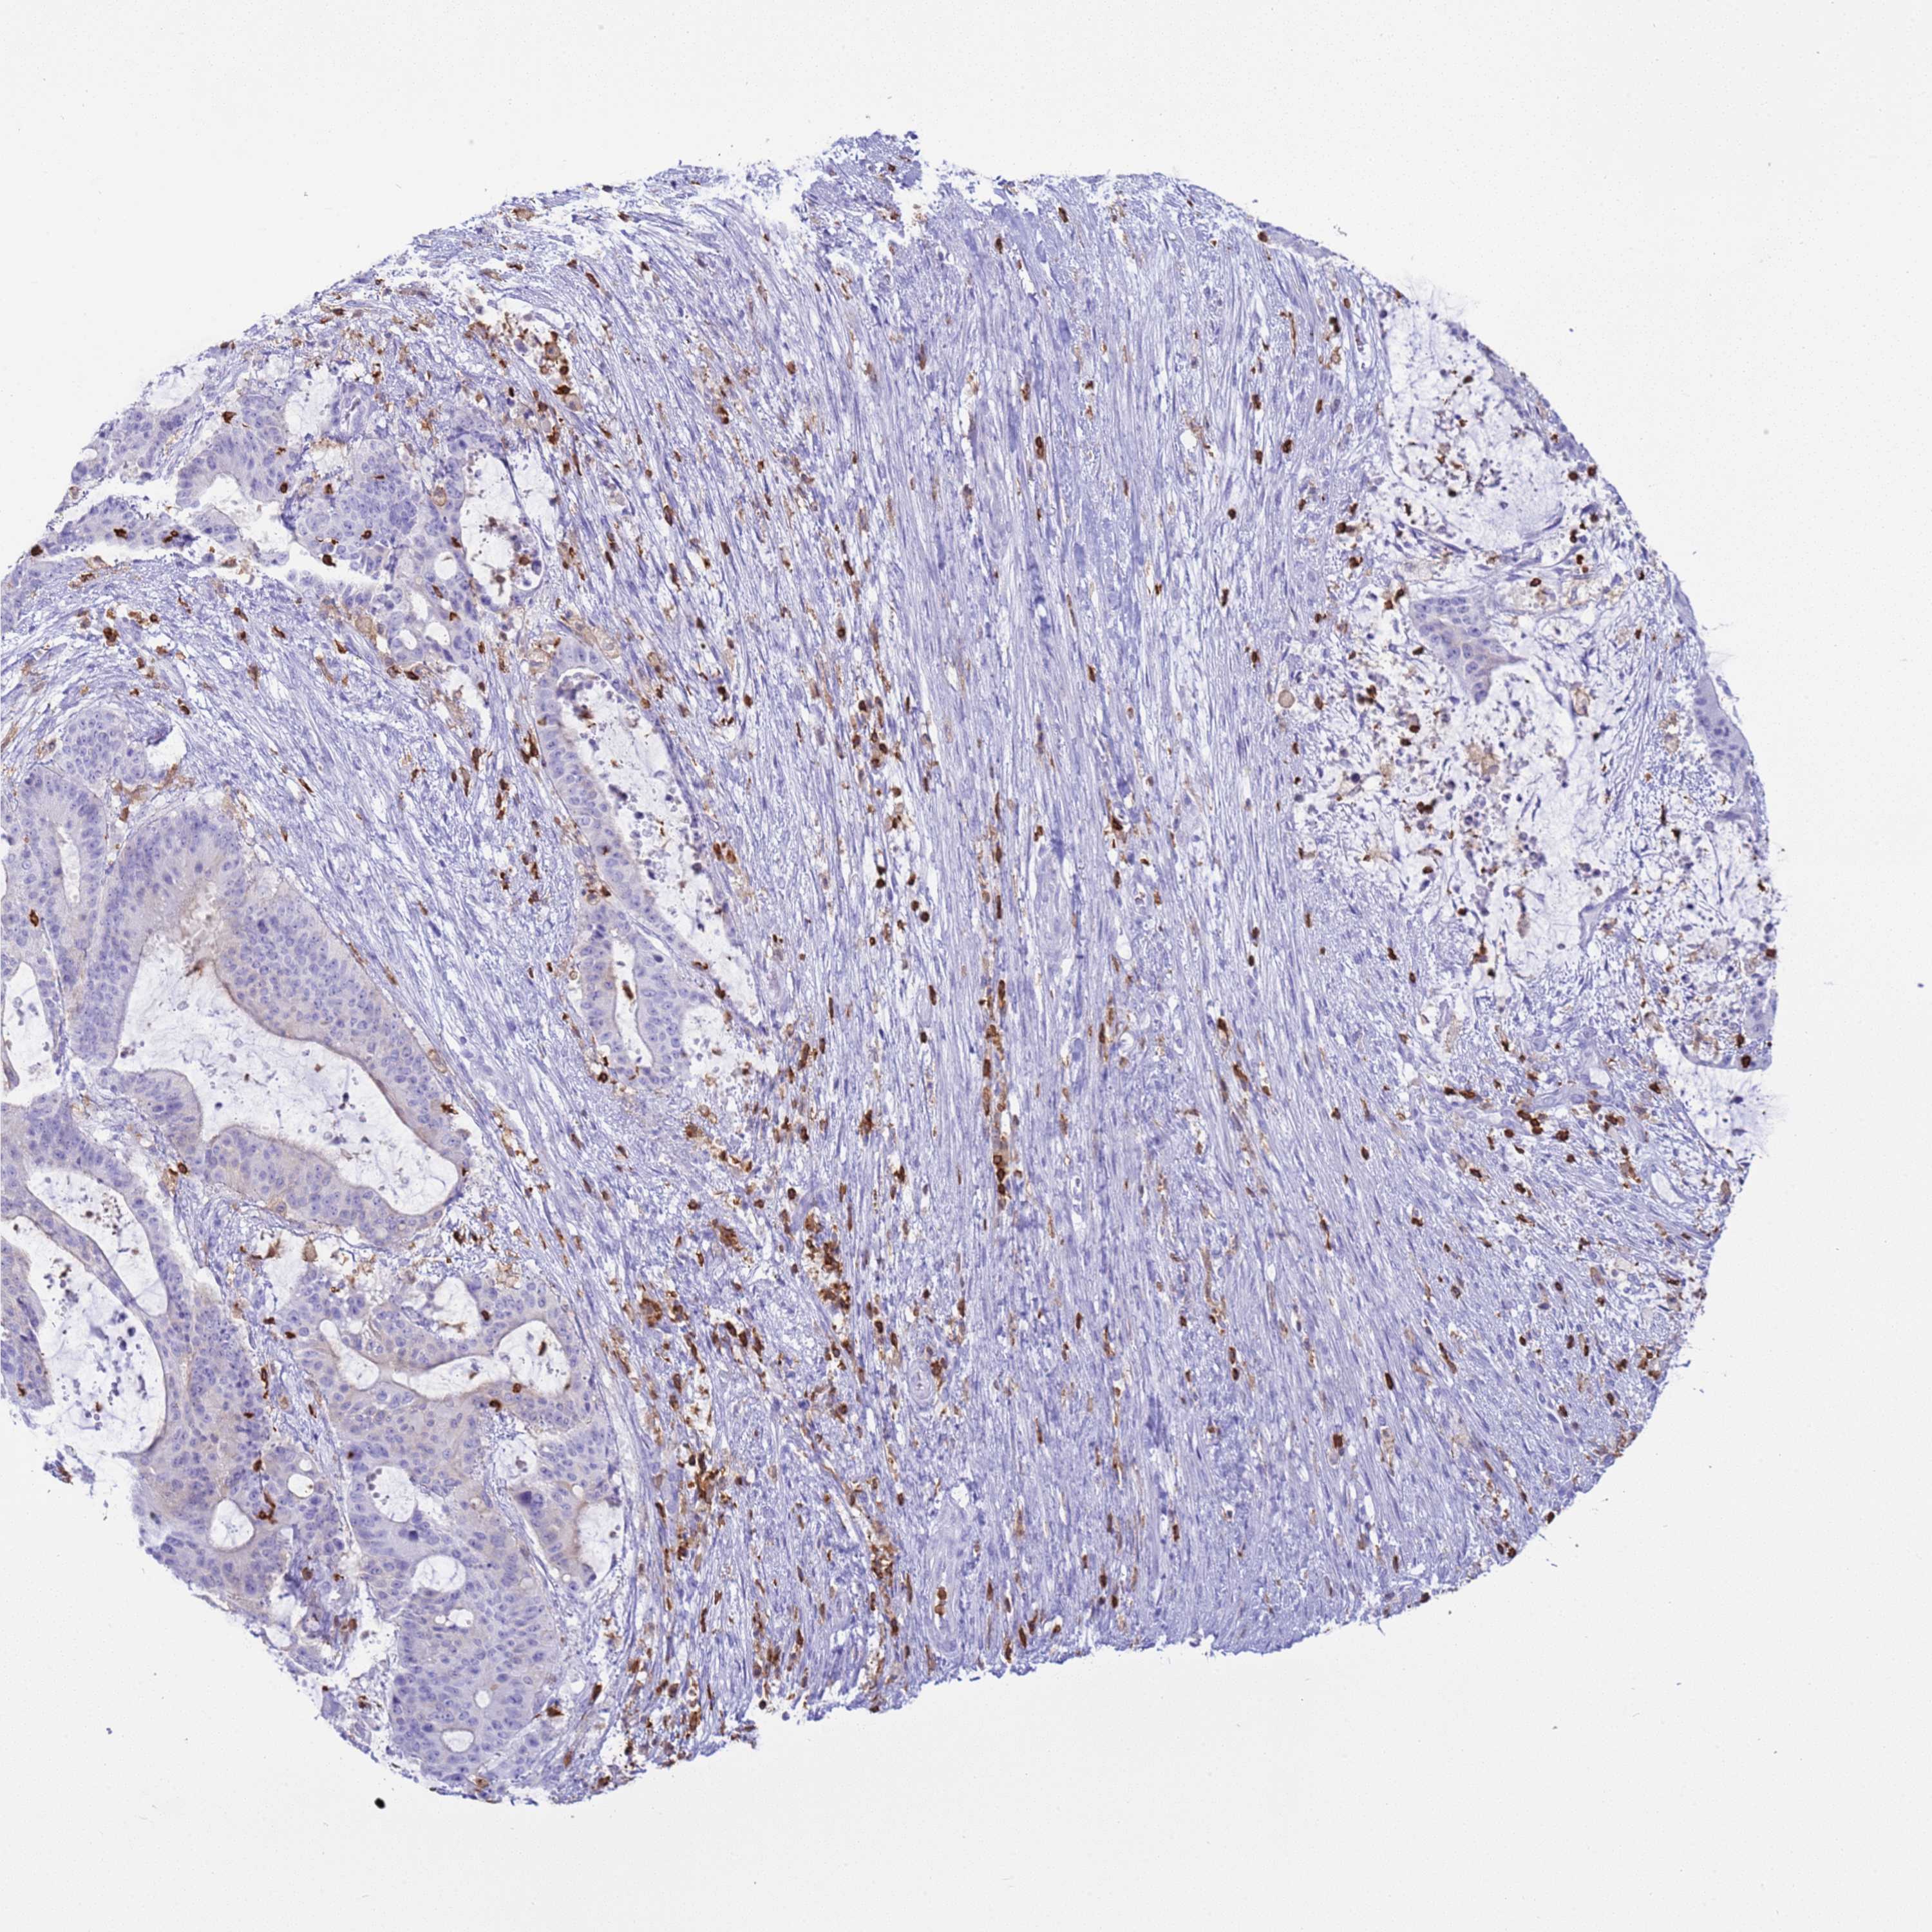

LIVER CANCER - Protein expressioni

A mouse-over function shows sample information and annotation data. Click on an image to view it in a full screen mode. Samples can be filtered based on level of antibody staining by selecting one or several of the following categories: high, medium, low and not detected. The assay and annotation is described here.

Antibody stainingi

Antibody staining in the annotated cell types in the current human tissue is reported as not detected, low, medium, or high, based on conventional immunohistochemistry profiling in selected tissues. This score is based on the combination of the staining intensity and fraction of stained cells.

Each image is clickable and will lead to virtual microscopy that enables deeper exploration of all samples and also displays staining intensity scores, fraction scores and subcellular localization as well as patient and tissue information for each sample.

Antibody HPA046700

Antibody HPA076024

Staining

High

Medium

Low

Not detected

Intensity

Strong

Moderate

Weak

Negative

Quantity

>75%

75%-25%

<25%

None

Location

Nuclear

Cytoplasmic/membranous

Cytoplasmic/membranous,nuclear

Cholangiocarcinoma

Carcinoma, Hepatocellular, NOS